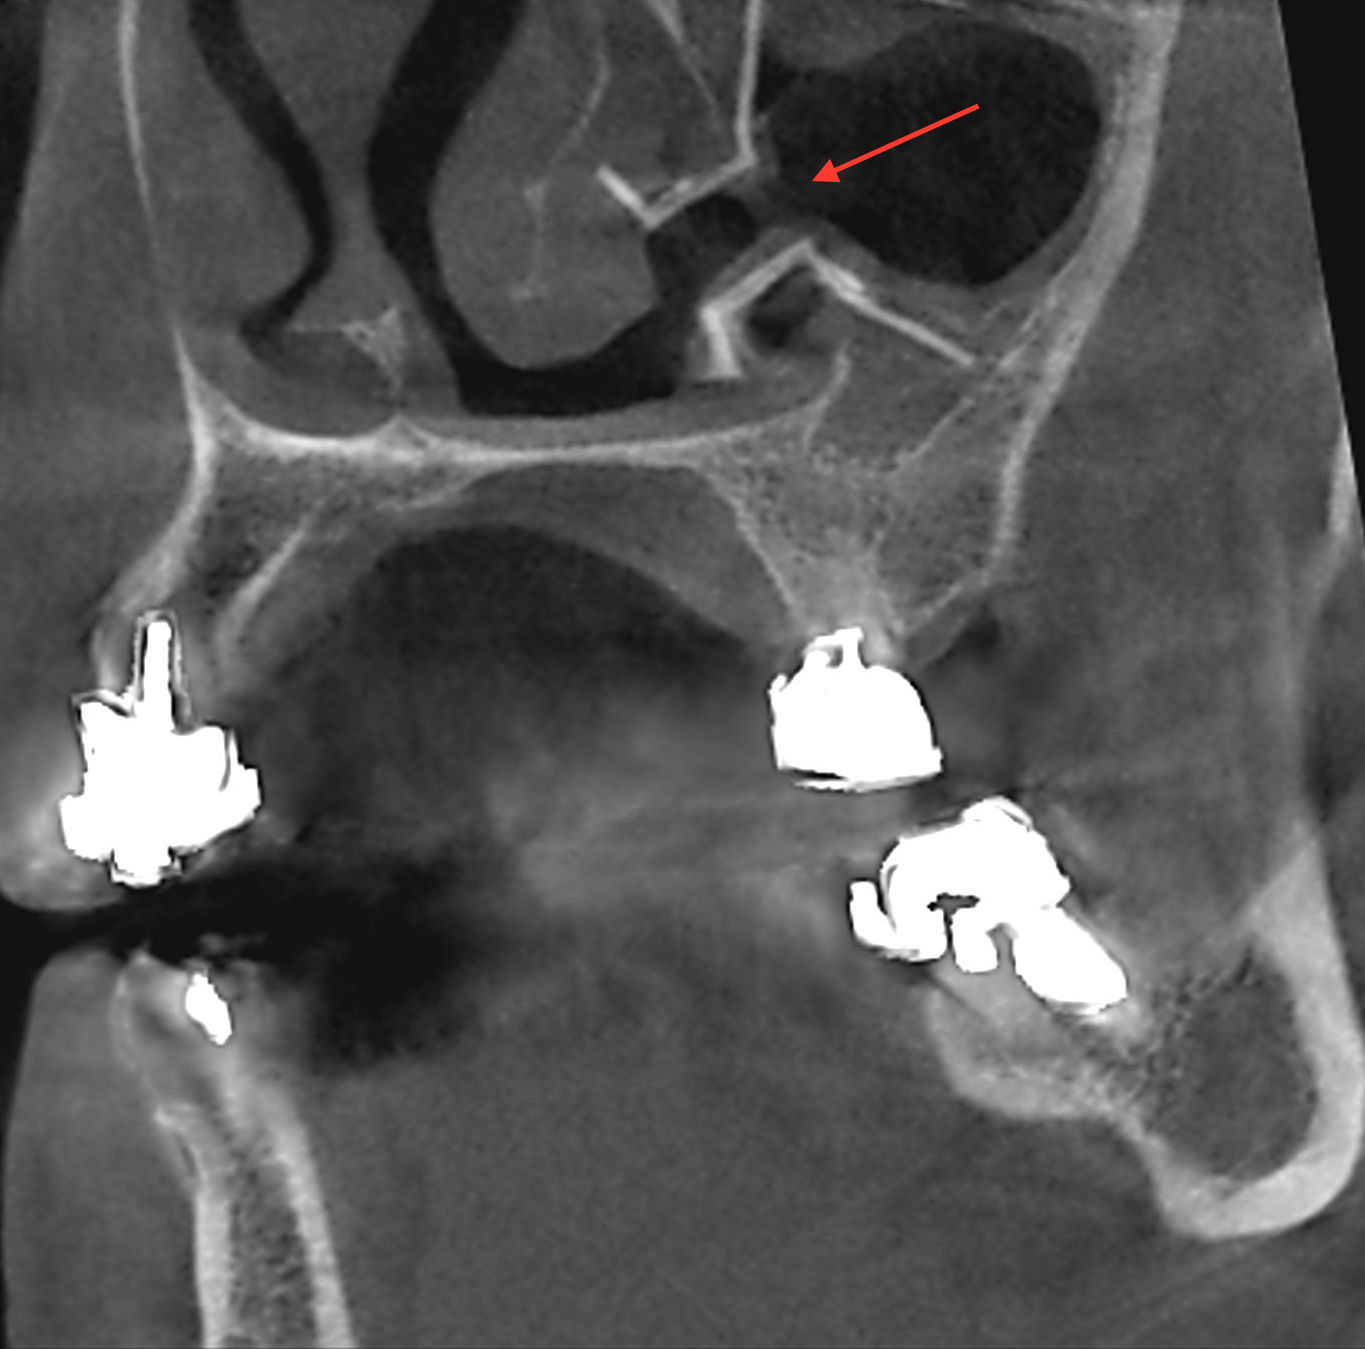

Les applications du cone beam dentaire sont donc nombreuses allant de la chirurgie buccale à l’orthodontie (télécrânes...), en passant par la chirurgie maxillo-faciale et l’ORL.

- pathologie des ATM (articulations temporo-mandibulaires)

- pathologie des sinus maxillaires

Les nouvelles générations de scanner permettent de faire une acquisition d’un volume global d’une partie du corps et de travailler à l’intérieur de ce volume en isolant une structure anatomique donnée et de l’explorer dans tous les plans de l’espace.

Grace à la technique de seuillage il est possible de dissocier progressivement les dents des structures osseuses environnantes dans le volume donné.